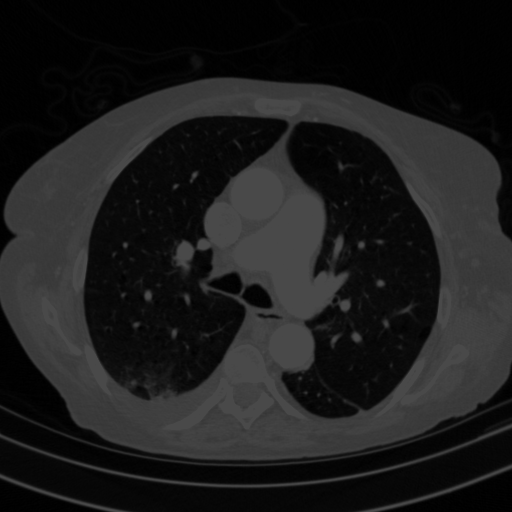

4Γ—3 grid: Rows show different image types (Original NATIVE, Reconstructed NATIVE, Original VENOUS, Generated VENOUS), Columns show windowing techniques (No Window, Lung Window, Mediastinum Window)

Reconstructed NATIVE CT scan (cycle consistency)

Lung window (WL -600, WW 1500 β†’ Low βˆ’1350, High +150)

Generated VENOUS CT scan (A→B translation)